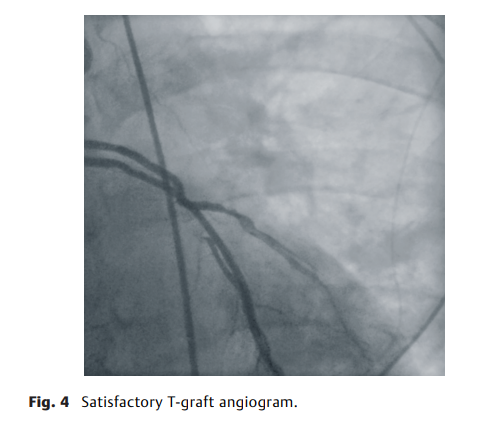

ICA 对3例患者(17%)的临床或手术决策有影响。在一名患者中,左胸内动脉 (LITA)的远端狭窄,因此进行双重抗血小板治疗6个月【图1】,两名 (11%) 患者进行了旁路移植物修复和额外的旁路移植术,这是由于一名患者的隐静脉移植物到钝缘支2阻塞【图2】,另一名患者有明显的 T 型移植物狭窄和移植物到左前降支阻塞【图3】。LITA。在这3例患者中,相应的外科医生认为ICA都优于TTFM。【图4】展示了令人满意的T型移植物血管造影。

图4. 令人满意的T型移植物血管造影。